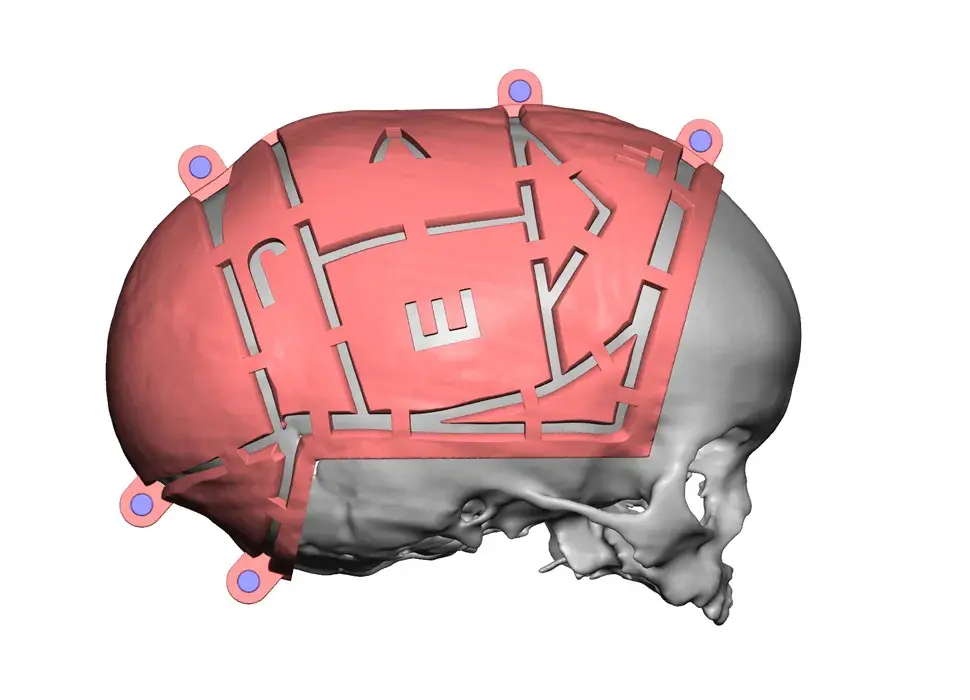

3D Systems' VSP® surgical planning solutions for craniomaxillofacial (CMF) applications received FDA clearance as a service-based approach to personalized surgery over 10 years ago.

3D Systems and Stryker Corporation have partnered to provide surgeons with best-in-class products and services for craniomaxillofacial surgeries. As a leader in personalized healthcare solutions, 3D Systems has planned and delivered devices for more than 140,000 patient-specific cases. The Stryker Craniomaxillofacial business specializes in providing patient-specific options and innovative solutions that help drive efficiencies in surgical suites. The combination of Stryker’s specialized team and advanced implants with 3D Systems' cutting-edge 3D printing technologies and expert consulting services positions both companies to provide a superior level of service to healthcare professionals who use these revolutionary solutions.